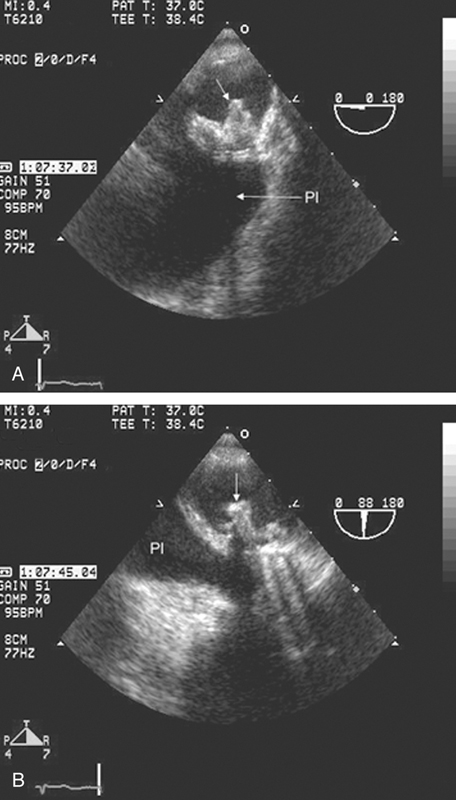

فحوصات تشخيصية لبعض امراض القلب والشرايين التاجية